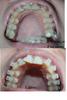

Недавно жаловалась на слабое движение...))) БЕРУ СВОИ СЛОВА ОБРАТНО))) Я просто пищу от восторга видя результат))) Сделала сегодня коллаж, но у не могу не поделиться с вами))) И это за месяц и 2 недельки))!!

img_y1_den-1_mes._2nedeli2235.jpg